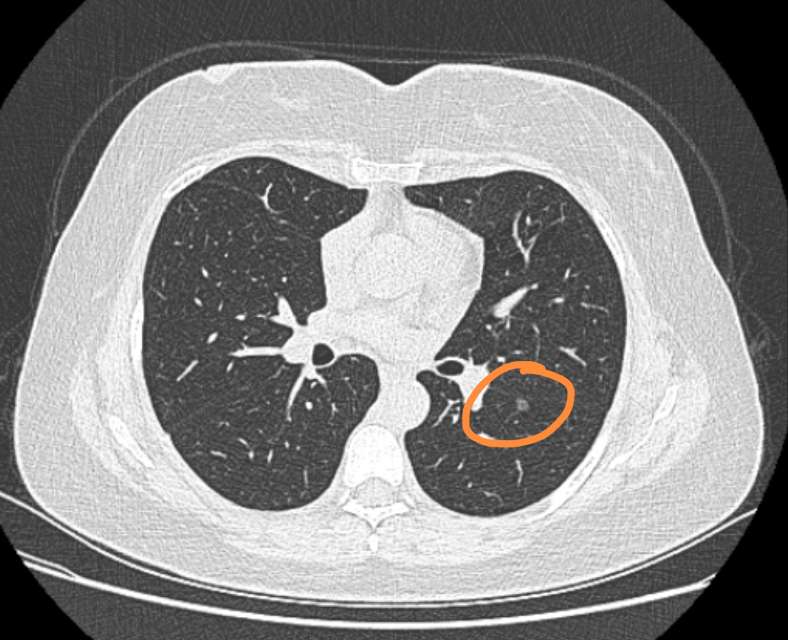

典型吸烟导致肺癌的ct图像,2.9cm肺结节,有毛刺,分叶, - 抖音